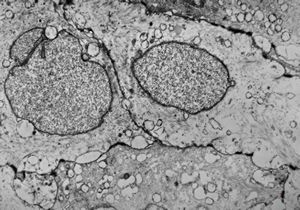

M,10y. | herpetic encephalitis